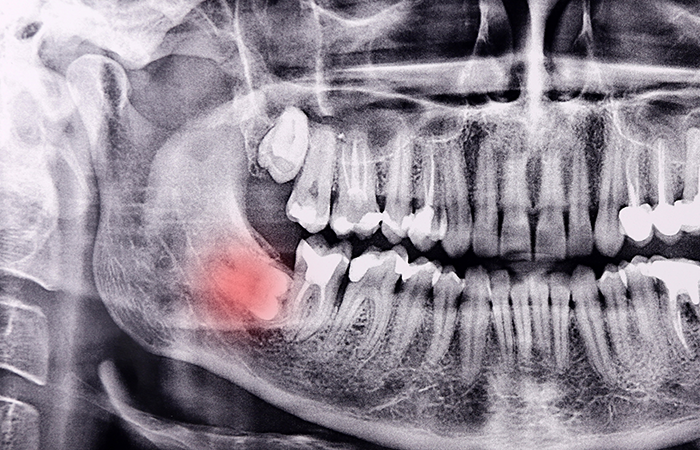

사랑니 발치